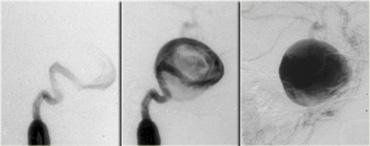

Đây là hình chụp mạch máu (angiogram) tương ứng.

Rõ ràng, đây không phải là tổn thương có thể phẫu thuật qua đường xuyên bướm (transsphenoidal)!

Đây là hình ảnh MRI của cùng bệnh nhân.

Khối có tín hiệu chủ yếu là đen và có một xảo ảnh dòng chảy lớn chạy theo hướng mã hóa pha.

Các đặc điểm này tương ứng với dòng máu chảy nhanh, do đó khối này phải là một túi phình động mạch.

Hình chụp mạch máu của cùng bệnh nhân.

Hình ảnh cho thấy dòng chảy trong túi phình không phải là dòng chảy tầng (laminar), mà là dòng chảy xoáy, lấp đầy dần lòng túi phình bằng thuốc cản quang.